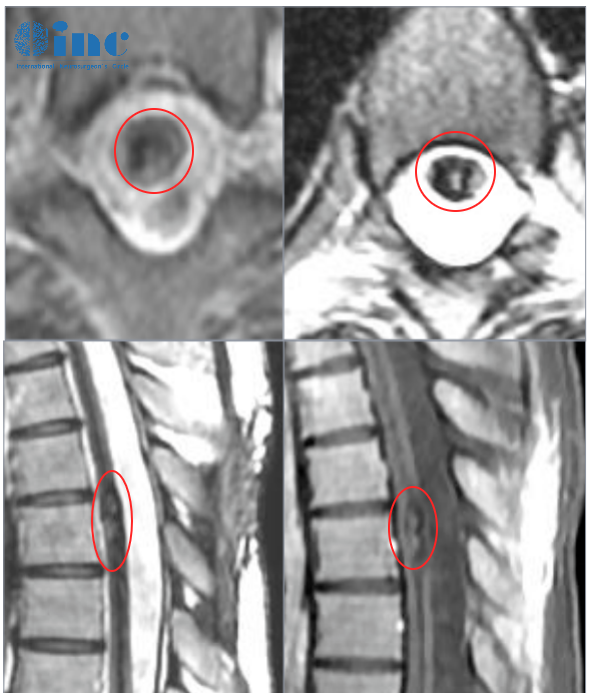

笑笑21岁,胸髓髓内海绵状血管瘤

病情的发展远远超乎我的想象。诊断后不久,我就出现了小便困难的情况,而且双腿的无力症状也在加重。再次来到医院,我只能坐在轮椅上,检查后,我被确诊为胸髓髓内海绵状血管瘤。

医生十分耐心地向我们解释,脊髓是大脑和周围神经传递信号的桥梁,主要分布在颈椎管和胸椎管。脊髓内代偿空间狭小,如果受到压迫或者出现空洞,传递信号的通路出现问题或者断了,就会出现严重的症状,甚至是瘫痪。

雪上加霜的是,由于我这个血管瘤的位置比较深,在腹侧,手术风险会更大,医生认为做完手术极有可能瘫痪,于是建议我保守观察。

他们为我找到了巴教授,教授对我们说,他的脊髓海绵状血管瘤手术并发症的发生率很低。这次手术的主要目标就是切除残留的血管畸形,以免将来的再次出血,我的行走问题可能在几周或几个月内有所改善,但也坦言可能无法完全恢复。